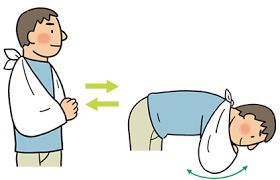

その方法は、三角巾をしたまま、肩の力を抜いて振り子の要領で、腕を前後させるようにします。慣れてくれば、肘で円を描くように動かしたりもします。

こうすることで、肩の周囲の筋肉が緊張することなくリハビリができるので、後の可動域を広げるリハビリに移行するときに有利になります。